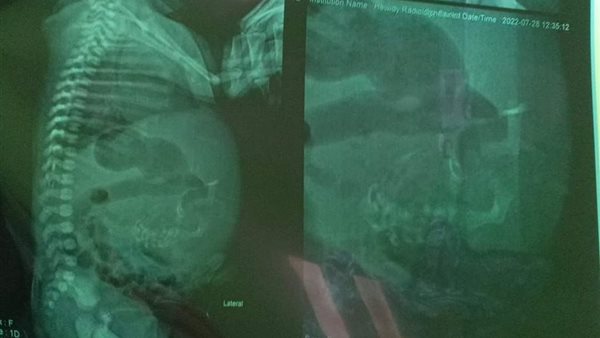

وأكد الدكتور أشرف الشرقاوي، مدير مستشفى الأطفال الجامعي بالمنصورة، أنه تم استقبال الطفلة أمس، وعمل أشعة رنين مغناطيسي وفحصها جيدا، وتحديد مكان الجنين داخلها، وجار تجهيز الحالة للجراحة لإزالته كاملًا.

وأجرت الأسرة أشعة تشخصية كشفت وجود جنين داخل بطن الطفلة، ولا يزال في بداية التكوين، وبعد قيام الطبيب بتشخيص الحالة، تم تحويلها إلى جراحة الأطفال بمستشفى طب الأطفال بجامعة المنصورة، لاتخاذ القرار الطبي المناسب.